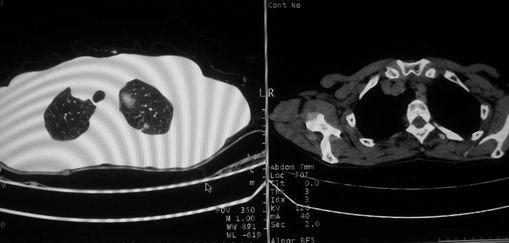

以下是引用zjzjr在2008-5-19 13:40:00的发言:[br]支持左上肺周围型肺癌(腺癌可能性大)伴颅内多发性转移.